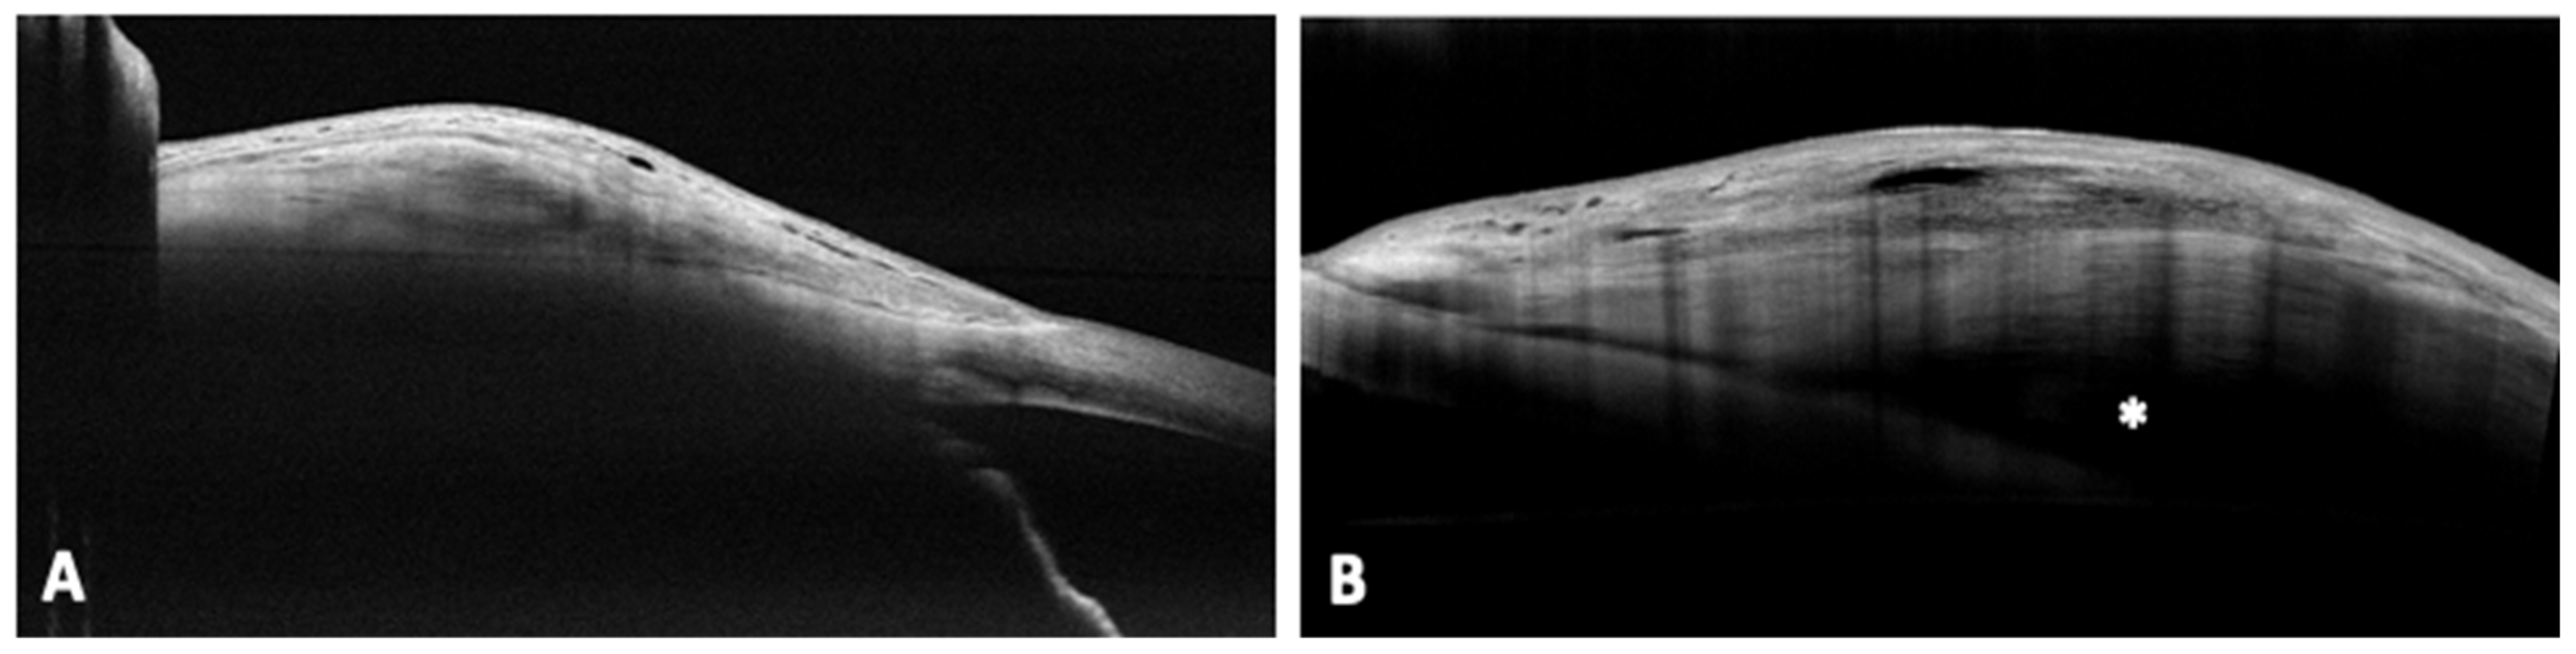

On the contrary, the most common morphology after PreserFlo procedure, at day 1, was the multiple internal layer (55%), which showed a tendency to reduce over time until it settled down around one third (37%), stable from month 1 onwards. At the last follow up PreserFlo’s most representative bleb was the microcystic multiform, whose percentage increased over time (17% at day 1 vs. 44% at month 6). The uniform pattern was well represented in our case series (7% at day 1 vs. 21% at month 6). Furthermore, all functional blebs in uniform subgroup featured the presence of an episcleral cavity, extending posterior to the limbus and seen as a nonreflective area between the connective tissue of the bleb wall and sclera. We denoted this cavity as the posterior episcleral fluid (PEF) lake. Example of bleb’s morphologies are visible in Figure 3.

Figure 3. AS-OCT image of a uniform bleb after 6 month from XEN implantation (A), and uniform morphology of a PreserFlo bleb with an associated PEF lake, indicated by the white asterisk, after 6 months (B). AS-OCT = anterior segment-optical cohernce tomography; PEF = posterior episcleral fluid.